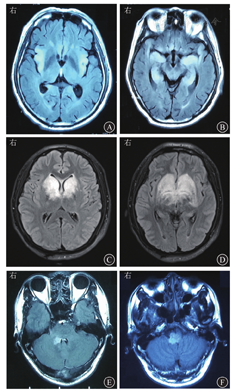

也称边缘叶脑炎,是最经典的脑炎临床综合征之一。边缘系统是位于脑室边缘的一系列灰质结构,其中位于颞叶内侧的海马区是边缘系统的重要结构。由于边缘性脑炎的累及范围局限于边缘系统,其脑炎症状也相对较少,以精神行为异常、癫痫发作(通常起源于颞叶)和近事记忆力障碍为主要症状,即边缘性脑炎的"三主症"。如患者具有"三主症"中的一种或者多种症状,同时脑电图发现颞叶起源的癫痫放电,或者头颅MRI发现单侧或者双侧的海马区病灶,即可诊断边缘性脑炎[6,7]。成人边缘性脑炎的最主要病因为单纯疱疹病毒1型(图1A和图1B)、单纯疱疹病毒2型、水痘-带状疱疹病毒(varicella-zoster virus, VZV)、CMV,人疱疹病毒6型(human herpesvirus 6,HHV6)也可引起边缘性脑炎,但相对少见[8]。自身免疫性边缘性脑炎相关的抗体包括抗富亮氨酸胶质瘤失活蛋白1(leucine-richg lioma inactiva-ted1,LGI1)抗体、抗谷氨酸脱羧酶(glutamic acid decarboxylase,GAD)抗体、抗Hu抗体等,部分患者合并肿瘤(副肿瘤性边缘性脑炎)。

基底节是位于大脑深部中线附近的灰质团块,基底节受累可导致智能减退、意识障碍、运动障碍等。基底节是病毒性脑炎常见的受累部位,以RNA病毒累及比较常见,例如乙型脑炎病毒、黄病毒、肠道病毒。在流行季节发生的基底节脑炎应首先考虑乙型脑炎(图1C和图1D)。2015年之后发现的斑松鼠博尔纳病毒脑炎[9]、嗜神经性星状病毒脑炎等都主要表现为基底节脑炎[10]。

脑干结构复杂,脑干损伤临床表现多样。可出现颅神经麻痹的表现,如复视、面瘫、听力障碍、吞咽困难、构音障碍等;锥体束受累可出现四肢瘫痪;网状结构受累可引起意识障碍,严重者累及延髓的循环与呼吸中枢。引起脑干炎的感染性病因包括肠病毒(成人相对少见)与VZV等,狂犬病毒主要累及脑干和边缘系统,其对延髓的选择性损伤导致中枢性的呼吸循环衰竭。单核细胞增生性李斯特菌对脑干也有一定的选择性(图1E和图1F),可以在脑干形成多发病灶与微脓肿[11]。脑干炎的自身免疫性病因包括炎性脱髓鞘病、神经贝赫切特综合征与Bickerstaff脑干炎等。